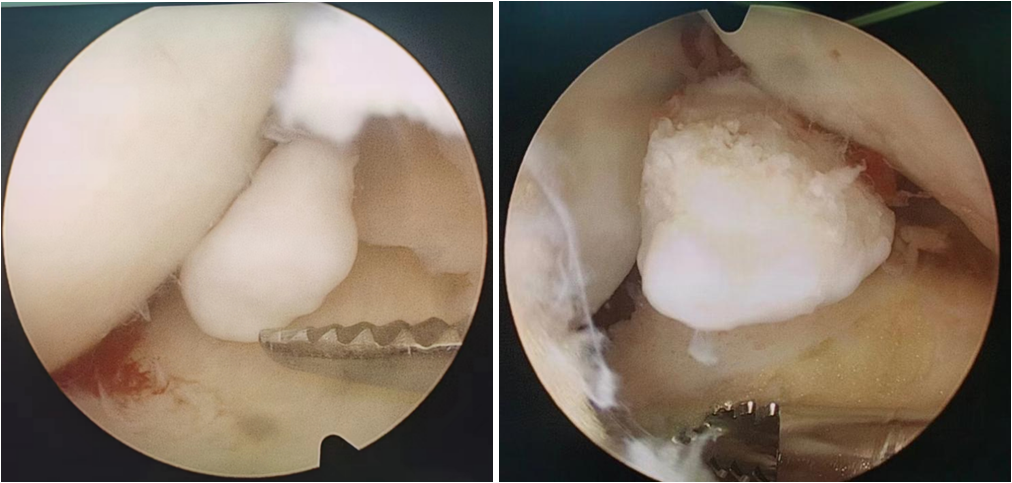

白大爷3年前开始发觉自己膝关节里有硬硬的东西,可以随着走路活动,时常还能听到关节内响声和感到错动感,甚至硬物会突然卡住关节,导致膝关节不能屈伸,活动之后呢这种情况又会消失。虽然每次下蹲和快走时都会小心翼翼,但由于症状能自行消失白大爷也没太在意,直到最近膝关节疼痛加重并能在髌骨上方摸到较大的硬块时才来医院看病,检查后才发现时膝关节内游离体,这种膝关节卡顿感就是游离体引起的关节绞锁现象。那么究竟什么是膝关节游离体呢,今天我们就来聊一聊。 膝关节游离体是什么? 膝关节游离体,是由于各种原因出现在关节腔内的游离的物体,是造成膝关节紊乱的常见原因之一,由于游离体有在关节内“窜走”的特点又被称为“关节鼠”。膝关节内游离体根据质地可分为骨性、软骨性、纤维性等,骨性和软骨性主要源自脱落的软骨、骨赘、骨折碎片以及损伤的半月板等,而纤维性的则主要继发于关节腔出血所致的血凝块和脱落的肥大滑膜绒毛等。各类创伤、退变和膝关节疾病导致的组织脱落都是关节游离体形成的原因,患者并不一定有明确的外伤史。 卡在关节间隙的骨性游离体(关节镜下) 膝关节游离体的表现 白大爷的体征是非常典型的,由于游离体的位置不固定,卡在关节狭窄处时会引起疼痛和关节绞锁,症状一般在活动后主动消失又反复出现,久而出现关节软骨、韧带损伤和关节积液,甚至引起慢性关节炎。 判断膝关节游离体最直观的检查就是X线片,可观察到关节腔内有大小各异的骨块,以圆形或卵圆形多见,可伴有关节边缘皮质骨密度增高。虽然磁共振很少用于检查游离体,但是它有利于排除其他相关疾病,如半月板撕裂和交叉韧带损伤。 X线见关节腔内巨大游离体 磁共振见髌上囊巨大游离体, 并排除半月板、交叉韧带损伤 那如何治疗游离体呢? 游离体在膝关节里面会磨损膝关节的软骨和肌腱、韧带,进而引起滑膜炎、关节积液、软骨磨损、半月板撕裂等一系列问题,并逐渐发展致膝关节变形、僵硬,疼痛难忍,甚至丧失正常生活和行走的能力。因此,早期治疗对防止软骨损伤很重要。在不太严重的情况下,物理治疗和抗炎镇痛药物等非手术治疗可能有助于保持膝关节的灵活性。然而,在大多数情况下,需要手术切除游离体。 关节镜治疗膝关节游离体,具有创伤小、疼痛轻、出血少、恢复快等特点,一般仅需两个洞孔即可有效清游离体及受损的软骨、半月板等,是目前关节腔内游离体摘除的首选治疗方案。因此,一旦明确膝关节内有游离体的存在,并且有明显的疼痛和功能影响,建议患者及早行微创手术摘除。 白大爷最终也在医生的建议下接受了关节镜下膝关节游离体摘除术,手术很顺利,伤口也很小,第二天白大爷就可以下地活动了,下蹲和疾走时再也不用小心翼翼,这种久违的顺畅感让白大爷很高兴。常规住院观察3天后,白大爷就开开心心的出院了。 白大爷关节内取出的游离体 作者:上海中医药大学附属岳阳中西医结合医院 骨伤中心 朱波 冯圣一 延伸阅读